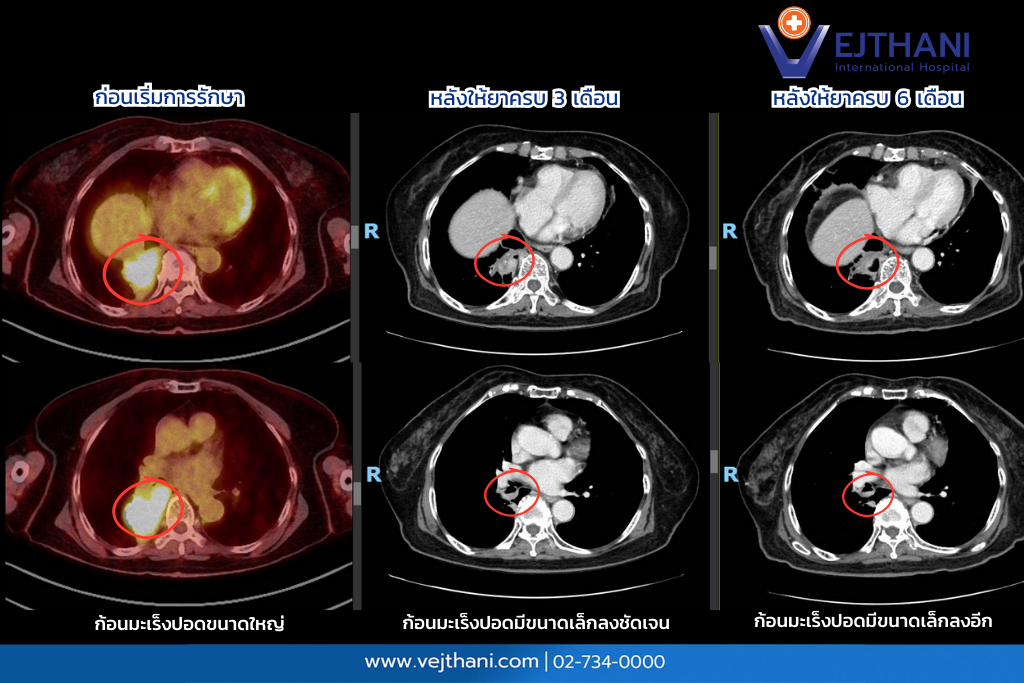

ผู้ป่วยรายนี้ได้รับการวินิจฉัยว่าเป็น มะเร็งปอดชนิด NSCLC ระยะลุกลาม และจากการตรวจชิ้นเนื้อพบการกลายพันธุ์ KIF5B-RET fusion แพทย์วางแผนการรักษาด้วยการให้ยา Selpercatinib ซึ่งเป็นยามุ่งเป้าในกลุ่ม RET inhibitor ในรูปแบบของยารับประทาน เป็นยาสูตรแรกที่ใช้ในผู้ป่วยรายนี้ โดยไม่ต้องใช้ยาเคมีบำบัด โดยผลการรักษาติดตามด้วยภาพถ่ายรังสีแสดงให้เห็นว่า

จากเคสผู้ป่วยรายนี้สะท้อนให้เห็นถึงความสำคัญของการตรวจหายีนกลายพันธุ์จากชิ้นเนื้อด้วยเทคนิค NGS หากผู้ป่วยไม่ได้รับการตรวจให้ครอบคลุมด้วยวิธีนี้ อาจตรวจไม่พบการกลายพันธุ์ RET fusion ซึ่งมีโอกาสพบได้น้อยมากเพียง 1 – 2% และอาจทำให้ผู้ป่วยพลาดโอกาสในการเข้าถึงการรักษาด้วยยามุ่งเป้าจำเพาะที่มีประสิทธิภาพสูงได้